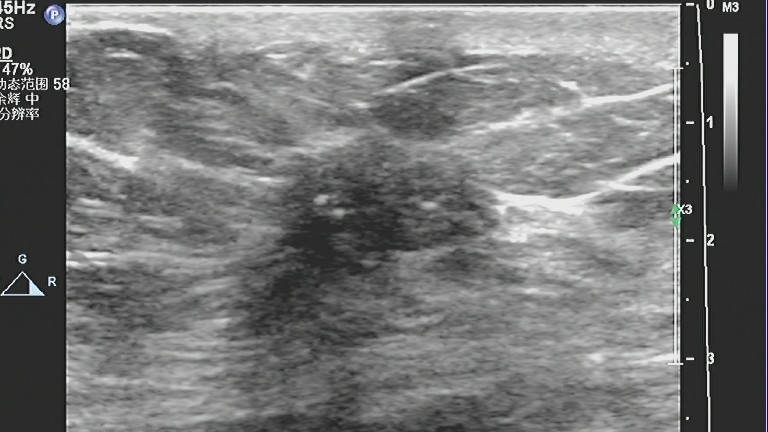

5、有微小钙化。